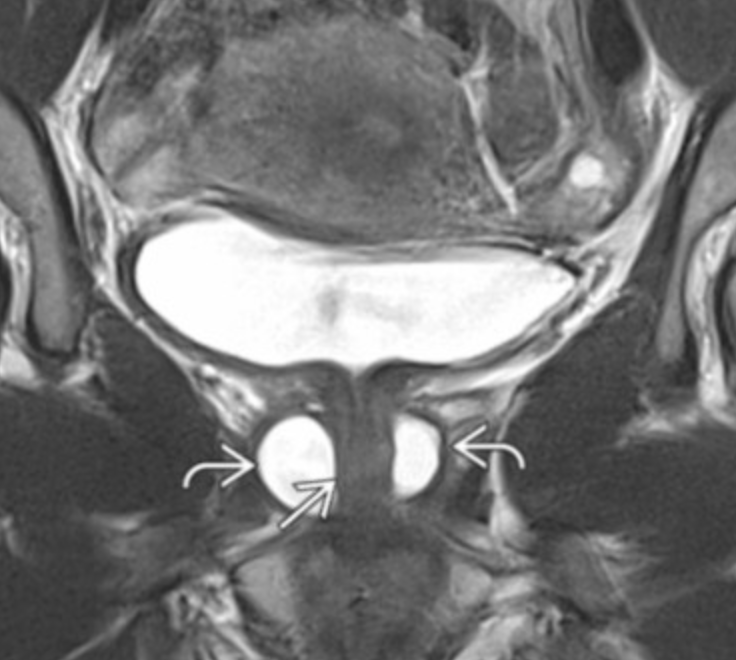

• Cystic fluid collection surrounding the urethra

• Complications

• Infection

• Stone formation

• Malignancy